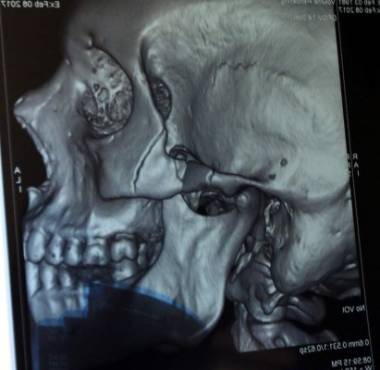

Escober mostrando la radiografía donde muestra el golpe en su pómulo.

Inmediatamente me hicieron radiografías y me informó que no era una lesión sencilla, pero manejable, el hueso estaba partido en tres partes y era necesario ponerme una platina y tornillos, que era lo mejor que tenía la tecnología, que iba poner todo de su parte para que saliera bien, gracias a Dios después de la operación recibí la buena noticia que no fue necesario poner la platina, todo quedó natural y ahora debo usar una máscara.